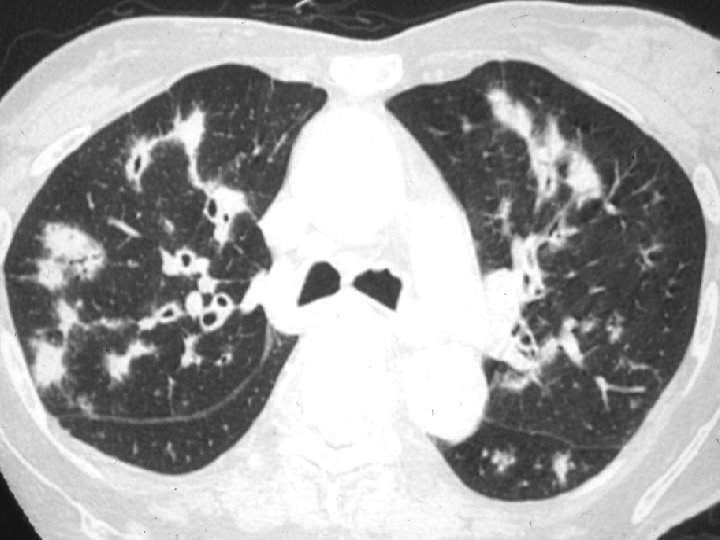

Radiologie: • Radiographies: – Poumons: • WG: Infiltrats interstitiels ou alvéolaires, parfois evanescents Nodules pouvant devenir cavitaires 34% des patients: infiltrats/nodules asymptomatiques • CSS: Infiltrats (surtout) evanescents chez 38 -70% Nodules: moins fréquents, moins tendance à cavitation Hémorragie alvéolaire: rare • PAM: Infiltrats alvéolointerstitiels 70%